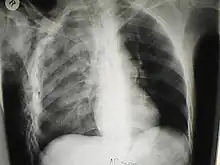

Diagnosis is by physical examination performed by a physician. The diagnosis may be assisted or confirmed by use of medical imaging with either plain X ray or CT scan.